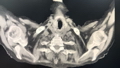

女,74岁

1990年房缺修补

1995年房颤射频消融术,术后复发

1998年发现丙肝

2008年脑梗

高血压35年

糖尿病18年

冠心病17年

心功能不全7年

肾功能不全3年